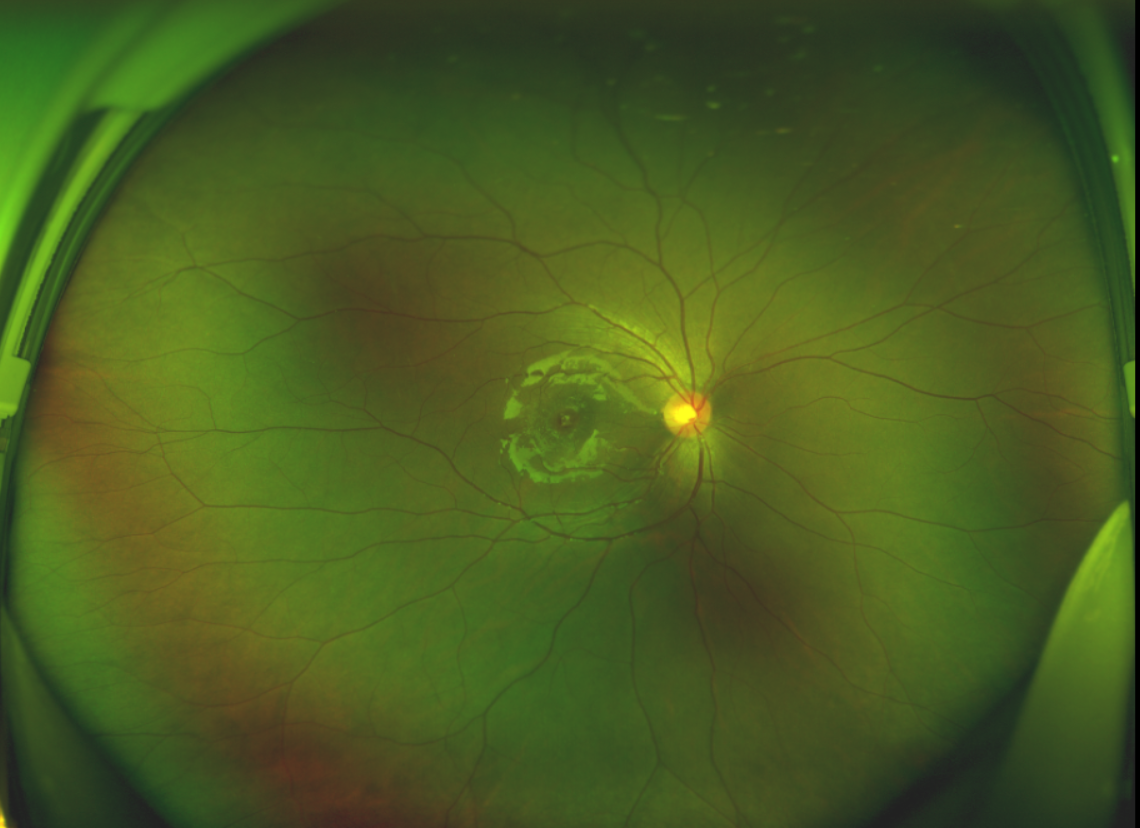

黃斑位于視網(wǎng)膜正中心,是視覺最敏銳的區(qū)域,堪稱“眼底的心臟”,負責我們閱讀、駕駛、識別人臉等精細視覺。 當黃斑區(qū)的神經(jīng)組織出現(xiàn)全層缺損,形成一個“孔洞”,即為黃斑裂孔,它會直接導(dǎo)致中心視力急劇下降、視物變形、視野中心出現(xiàn)暗區(qū)。

由于裂孔較小,當?shù)蒯t(yī)院建議先觀察,看看裂孔是否能夠自愈??砂肽陼r間過去了,誠誠傷眼的裂孔不僅沒有愈合的跡象,反而越來越大,這讓家長的心揪得更緊了。

除此之外,利用自體組織覆蓋為黃斑裂孔提供了理想的愈合環(huán)境,裂孔閉合速度顯著快于傳統(tǒng)方法。誠誠接受手術(shù)24小時后,檢查可見內(nèi)界膜瓣位置良好;術(shù)后1個月,黃斑裂孔已經(jīng)閉合,視力恢復(fù)到0.5;術(shù)后兩個月,視力進一步提升到0.7。